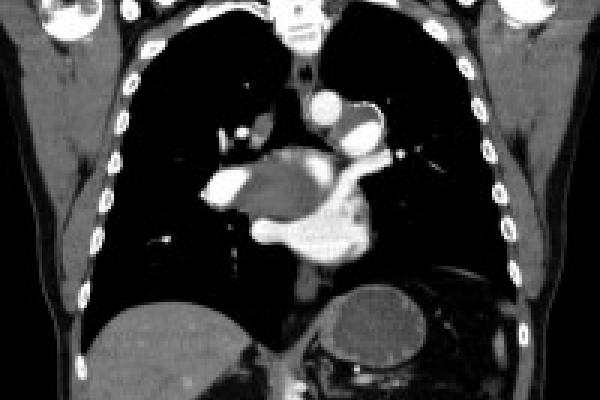

Extensive chronic clot removed from both of Kevin's lungs

Extensive chronic clot removed from both lungs.

• Kevin underwent successful PTE surgery with extensive chronic clots removed from both lungs on a Monday and was discharged on a Saturday.

• His pulmonary hypertension resolved and, with the obstructions removed from his pulmonary artery, the right side of his heart, which had become enlarged, returned to normal size.